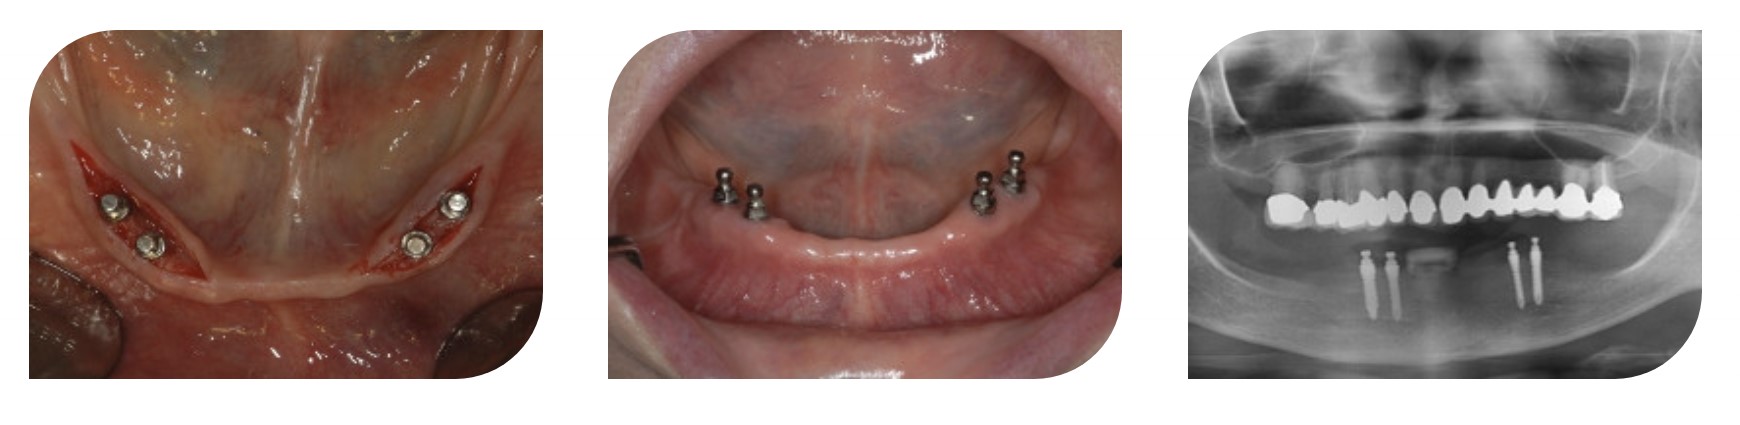

Имплантация через 7 месяцев